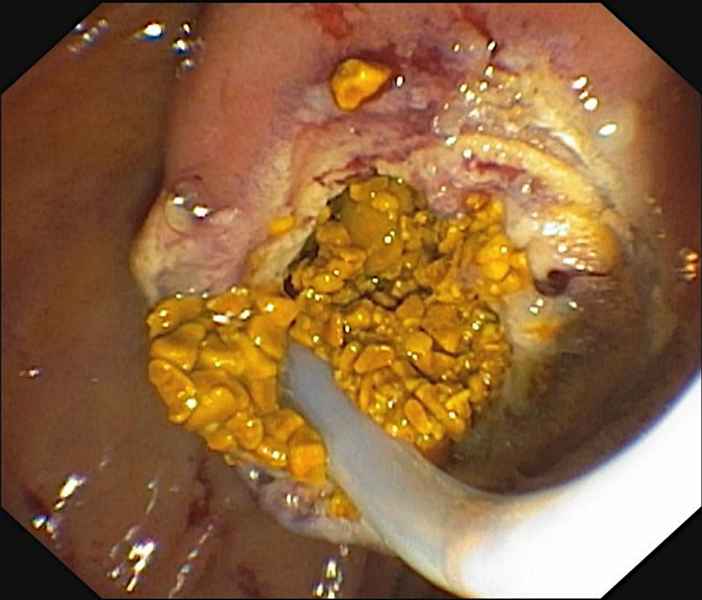

A case of pancreatic tuberculosis